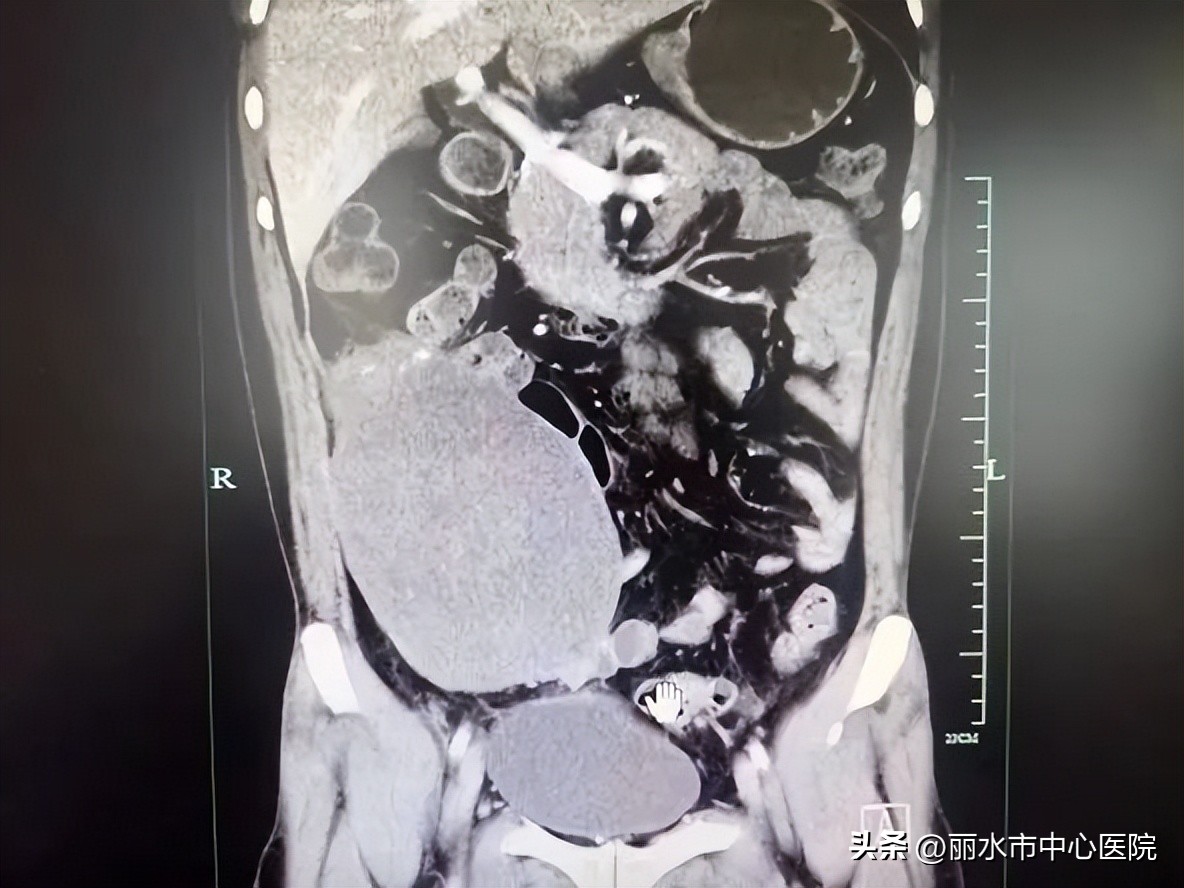

患者王某因“发现腹腔肿物5年,腹胀10余天”来我院门诊就诊,初见患者犹如妊娠数月的孕妇,首诊医生心生疑虑,该患者不简单,立即为患者进行体格检查,患者腹部可明显触及一巨大包块,接着进一步查腹部增强CT提示“腹盆腔巨大肿瘤,考虑平滑肌肉瘤可能,伴肠系膜、后腹膜、盆腔及右心膈角多发淋巴结肿大,考虑肿瘤转移”。

来院时腹部CT